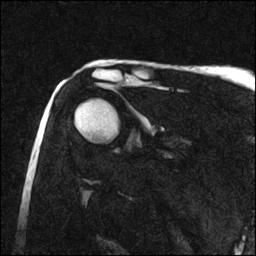

| Numero della serie: | 5 | Descrizione della serie: | GEFS COR |